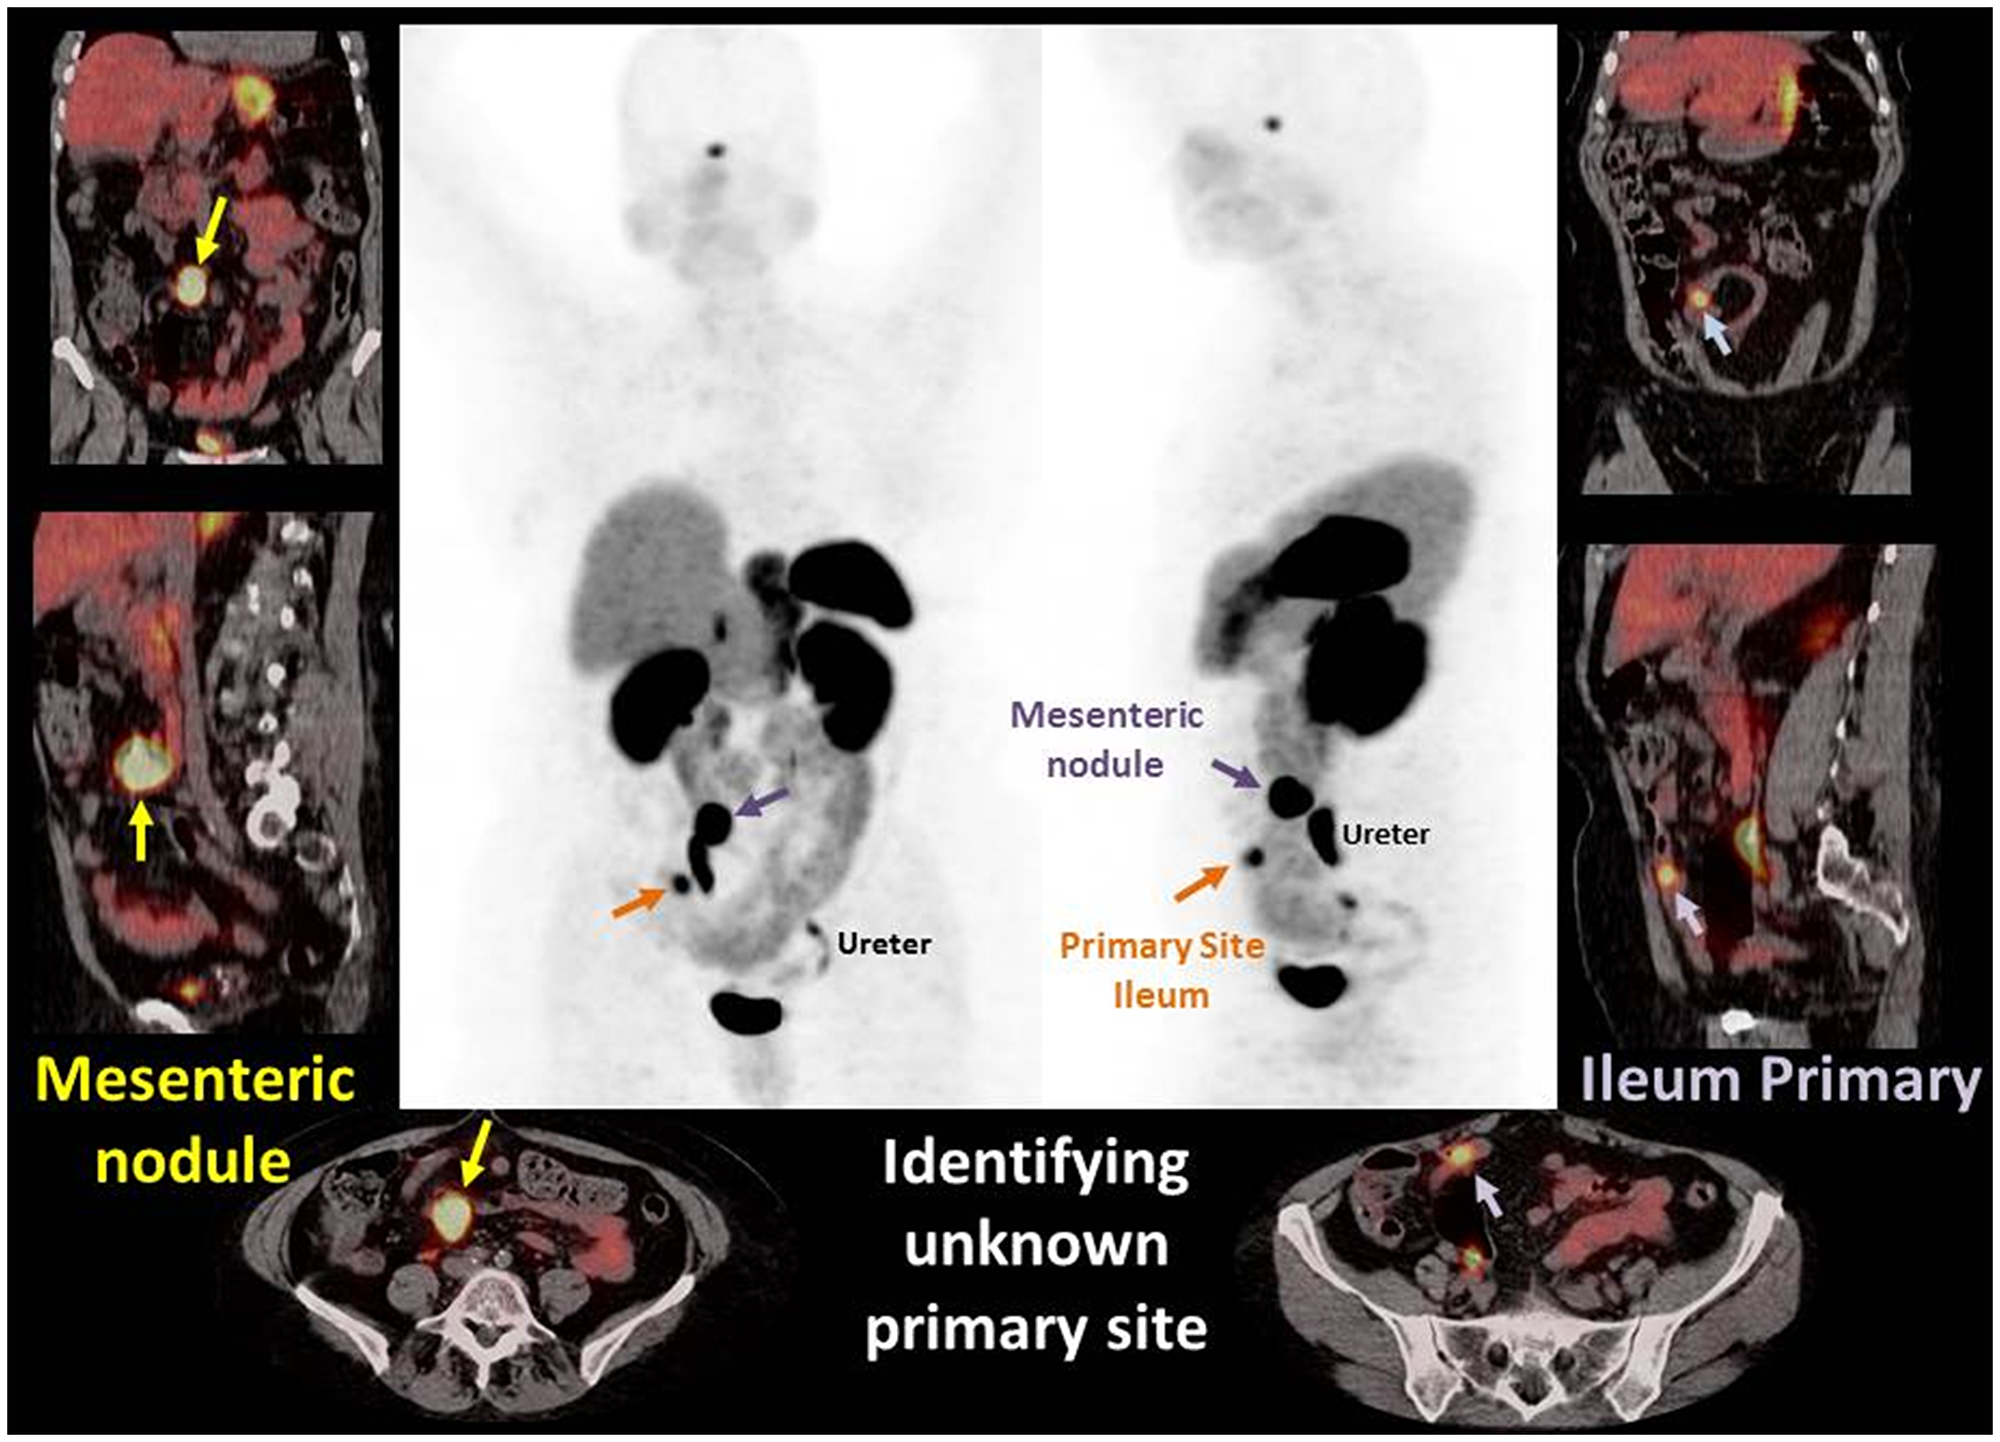

We performed analyses to determine if gallium-68 DOTATATE imaging could identify primary tumors that were otherwise deemed NET of unknown primary. For the purpose of the study we defined the unknown primary as a tumor of whose origin was not established after CT and or MRI scan, upper GI endoscopy and colonoscopy. Within the cohort, 38 patients were diagnosed with NET of unknown primary, and the gallium-68 DOTATATE imaging located primary tumors in 17 of 38 (44%) patients. Figure 2. Images demonstrate PET MIP images and fused PET/CT axial, sagittal, and coronal images of a case example of gallium-68 DOTATATE identifying unknown primary site. A 70 year old female patient presented to the emergency department with abdominal pain. Contrast CT of the abdomen and pelvis showed an irregular mesenteric mass and no primary identified. Gallium-68DOTATATE PET/CT demonstrated an avid mesenteric mass and identified an avid ileal primary. Subsequently the patient underwent exploratory laparotomy with small bowel resection and mesenteric node dissection. Pathological examination revealed a well differentiated G2 neuroendocrine tumor. This case highlights capability of gallium 68-dotatate imaging in locating the primary tumor which was otherwise missed in anatomic scans (Contrasted CT scan).

Figure 2: Images demonstrate PET MIP images and fused PET/CT axial, sagittal, and coronal images of a case example of gallium-68 DOTATATE identifying unknown primary site. A 70 year old female patient presented to the emergency department with abdominal pain. Contrast CT of the abdomen and pelvis showed an irregular mesenteric mass and no primary identified. Gallium-68DOTATATE PET/CT demonstrated an avid mesenteric mass and identified an avid ileal primary. Subsequently the patient underwent exploratory laparotomy with small bowel resection and mesenteric node dissection. Pathological examination revealed a well differentiated G2 neuroendocrine tumor. This case highlights capability of gallium 68-dotatate imaging in locating the primary tumor which was otherwise missed in anatomic scans (Contrasted CT scan).